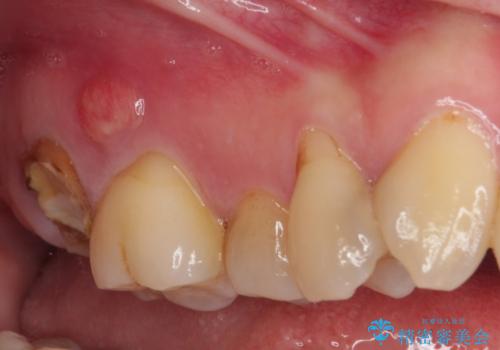

- 長年放置しているむし歯を気にして来院された患者様です。

外側を向いている上顎の奥歯は歯ブラシが十分に届かないため、むし歯となるケースが多いのですが、今回むし歯となってしまった歯がそれで、ボロボロになって根だけが残っている状態でした。

患者様と相談し、抜歯をした上でインプラントによる補綴治療を行うこととしました。